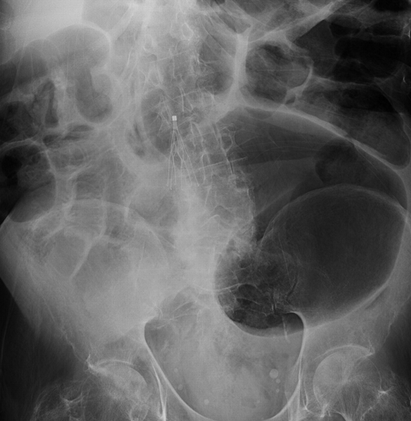

Απλές ακτινογραφίες κάτω άκρων, γονάτων και σφυρών. Ορατές ουσιώδεις ασβεστώσεις στην οπίσθια κνημιαία αρτηρία και ένα δίκτυο μικρών αγγείων στην οπισθοσφυρική περιοχή. Στα γόνατα, το αρθρικό διάστημα παρουσίαζε εμφανή ασβέστωση μικρών αγγείων. (Ευγενική παραχώρηση Dr. V. Penopoulos).